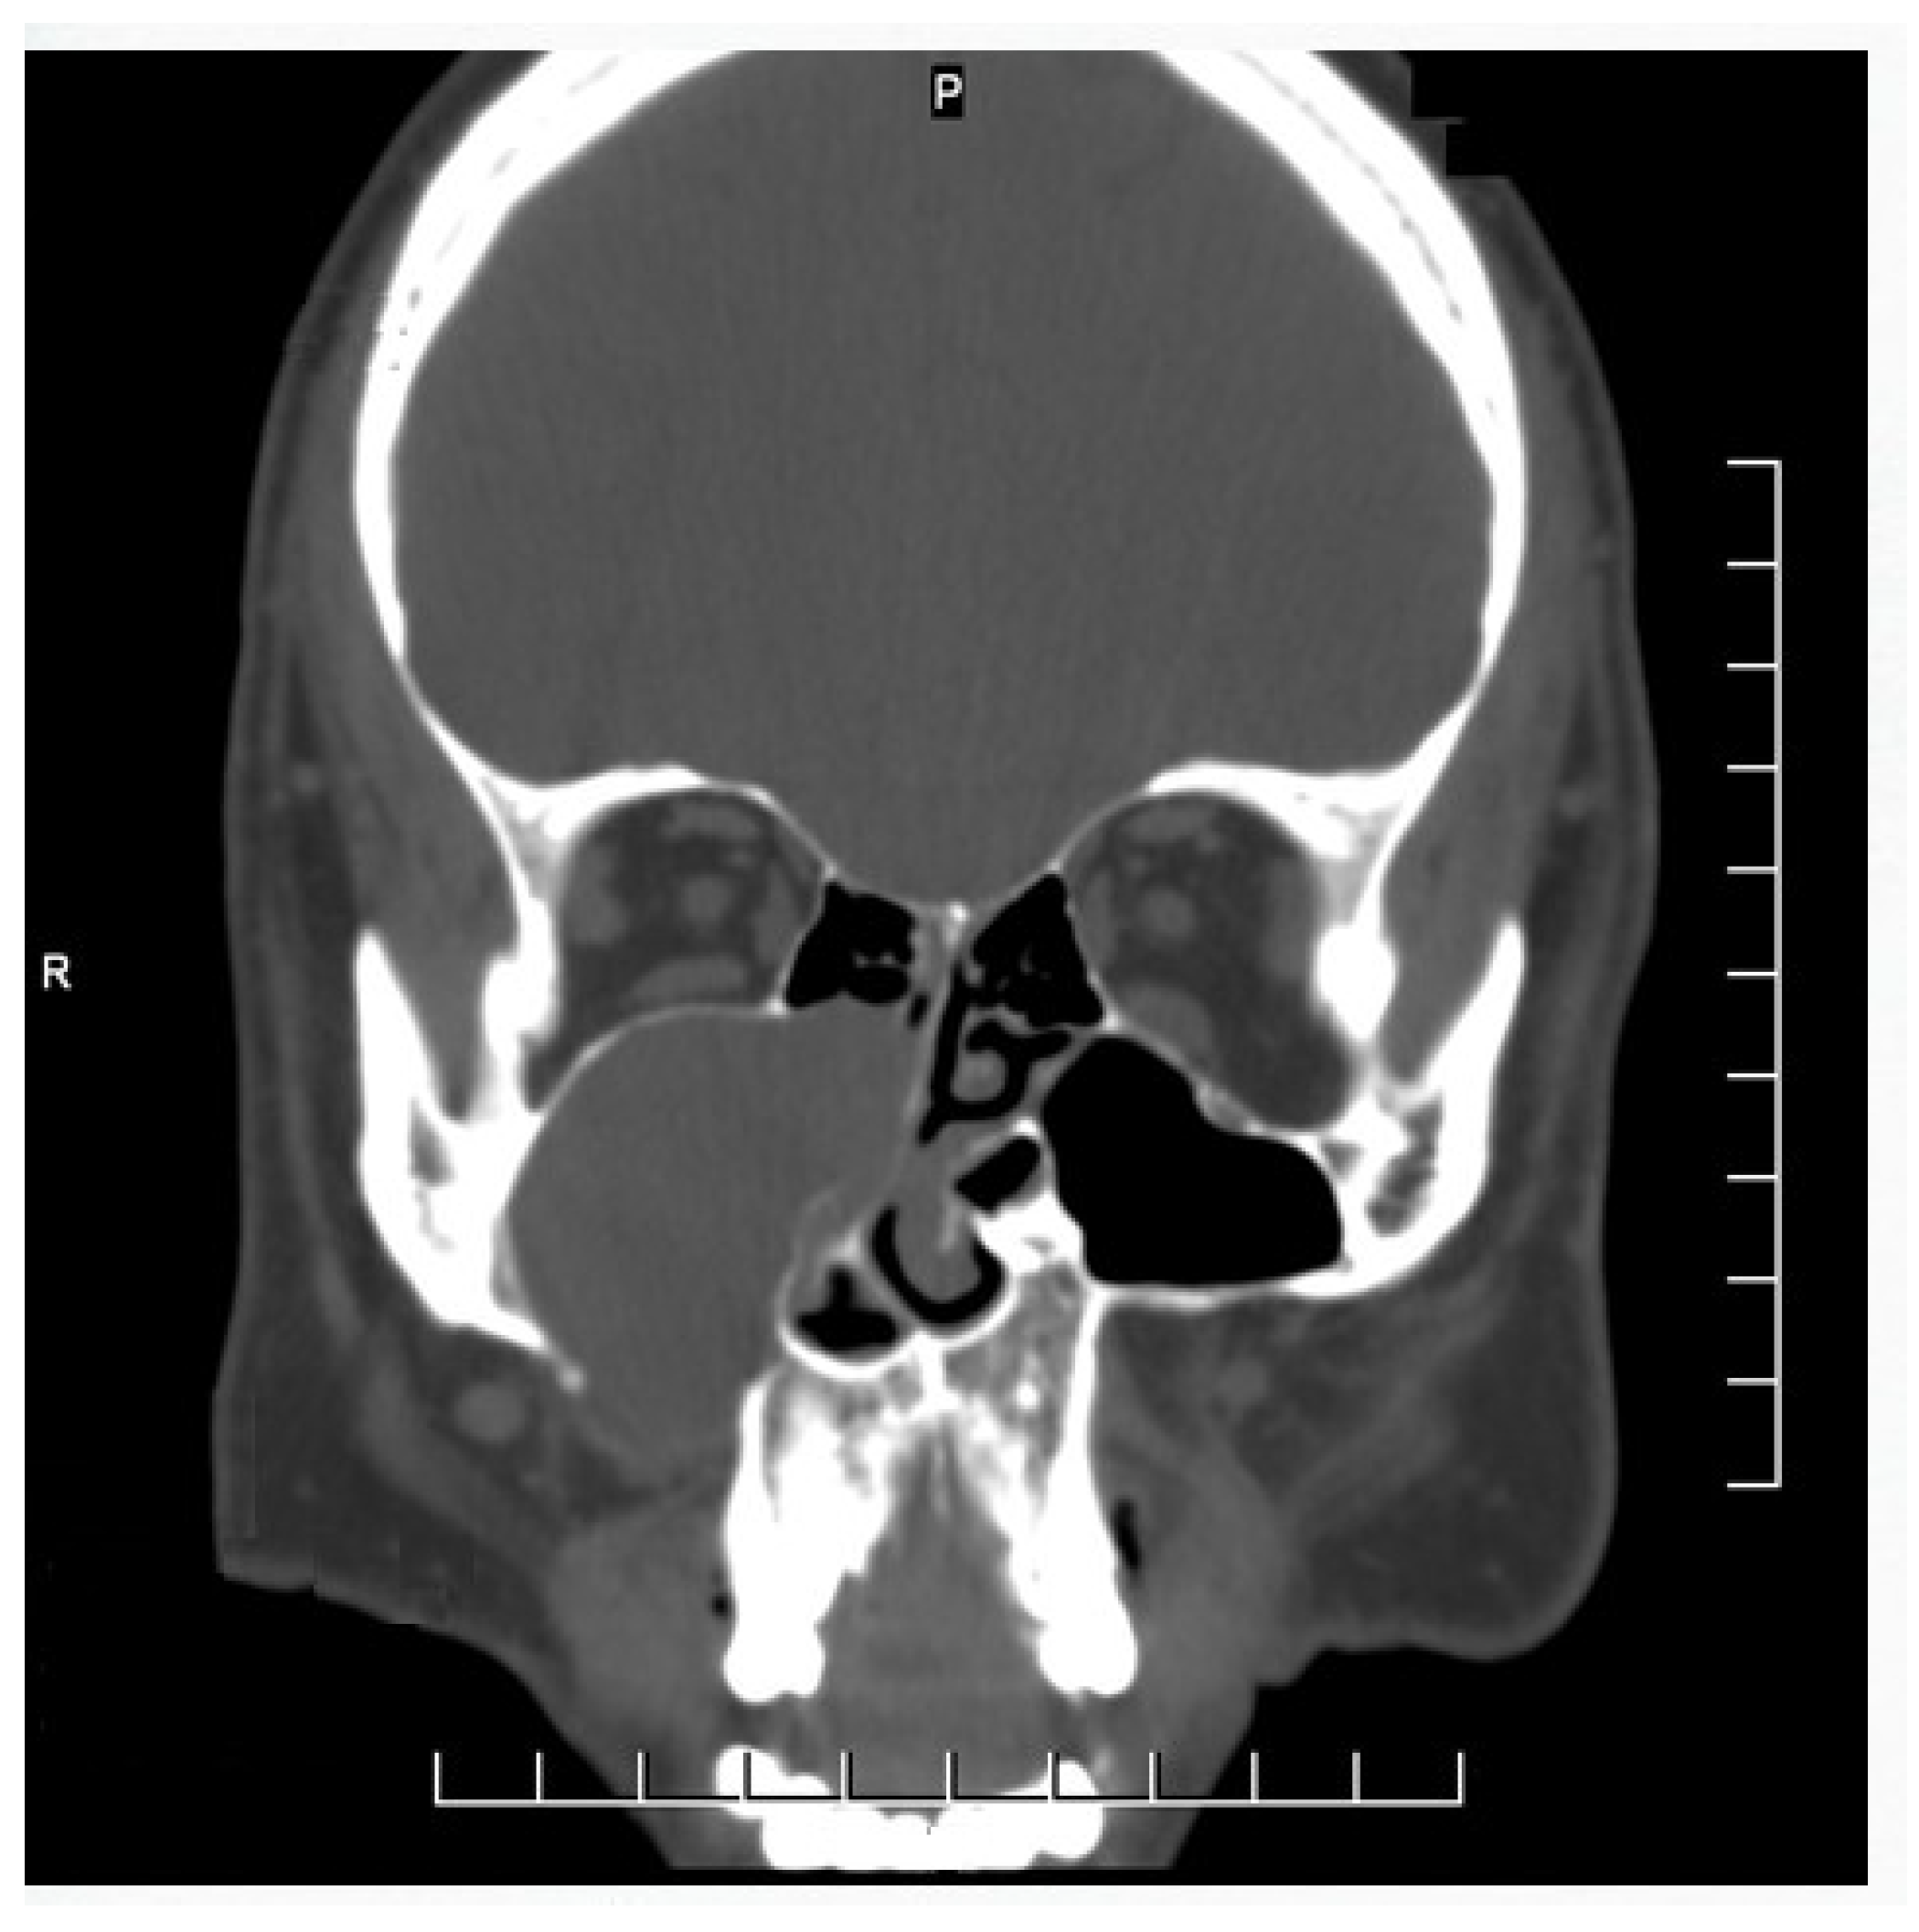

Surgical Technique